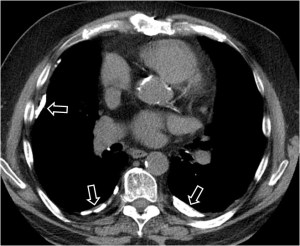

Esta segunda imagen corresponde a ascitis. Observa como la interfase entre el bazo y el líquido (flecha) es más nítida que en la imagen anterior. También lo es la interfase entre el hígado y el líquido.

En la imagen correspondiente a ascitis que presentamos en el signo anterior, observa cómo se respeta la zona posteromedial del hígado.